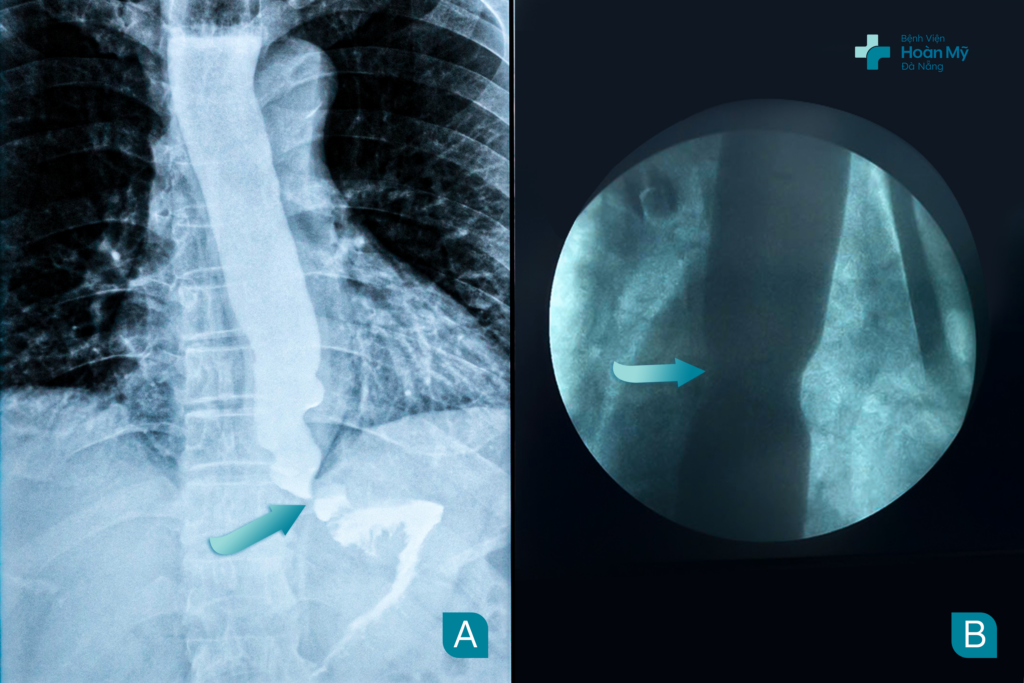

Hình (A) - trước nong, Hình (B) – Sau nong

Thực quản hẹp tắc được khơi thông sau nội soi nong hẹp thực quản bằng bóng

Nong thực quản qua nội soi là kỹ thuật đưa bóng nong vào phần vị trí hẹp của thực quản qua nội soi, sau đó từ từ bơm bóng và theo dõi dưới màn hình X-quang làm rộng phần bị hẹp của thực quản và được áp dụng trong trường hợp hẹp thực quản hoặc co thắt tâm vị thực quản. Phương pháp này khá an toàn, nhanh chóng và cho hiệu quả điều trị cao.